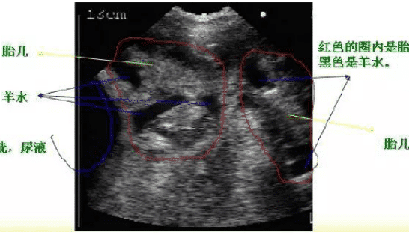

獸用B超機_懷孕母豬B超圖像講解

獸用B超機使用方法--母豬妊娠檢測